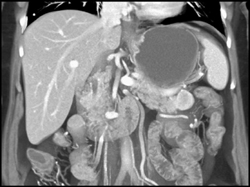

Neurogenic Tumor Near the Pancreatic Tail